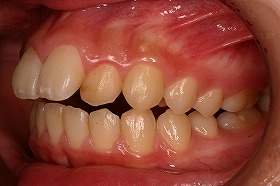

東京世田谷矯正歯科センターで、治療を進めると

出っ歯も後ろに下がり、噛み合わせもキレイになりました。

さらに上の歯が下の歯とあたるようになり、

とても食事がしやすくなったと喜んでいました。